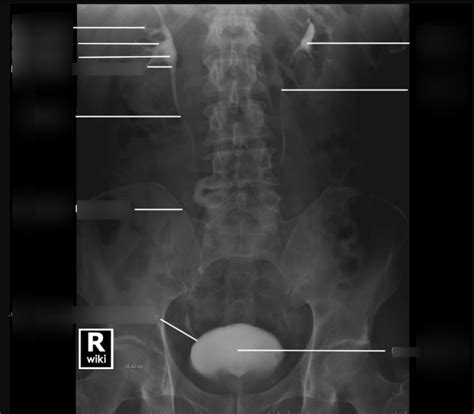

Hey guys! Let’s dive into the fascinating world of IVP anatomy. IVP, or Intravenous Pyelogram, is a radiological procedure used to visualize the urinary system. To really understand what’s going on during an IVP, it’s super important to have a solid grasp of the anatomy involved. So, let’s break it down in a way that’s easy to digest. We’ll explore each component, its function, and why it matters for a successful and informative IVP. Knowing your anatomy is half the battle, right? So, buckle up, and let’s get started!

The kidneys are bean-shaped organs located in the abdominal cavity , towards the back. Most people have two kidneys, sitting on either side of the spine. These incredible organs are the primary filters of your blood. Blood enters the kidneys through the renal arteries , and inside, it’s filtered through tiny structures called nephrons. Each kidney contains about a million nephrons! These nephrons remove waste products like urea, creatinine, and excess salts, while also reabsorbing essential substances like glucose, amino acids, and water back into the bloodstream. The filtered waste, now called urine, is then collected and channeled out. The purified blood exits the kidneys through the renal veins . The kidneys aren’t just about filtration; they also play a vital role in regulating blood pressure, producing hormones like erythropoietin (which stimulates red blood cell production), and maintaining electrolyte balance. Proper kidney function is essential for overall health, and any issues here can have widespread effects on the body. During an IVP, the contrast dye is filtered by the kidneys, allowing radiologists to visualize their structure and function. This helps in identifying any abnormalities, such as blockages, tumors, or structural issues. Understanding the kidney’s anatomy – its outer cortex, inner medulla, and the renal pelvis – is key to interpreting IVP images effectively.

The ureters are muscular tubes that connect the kidneys to the bladder. Think of them as the urine’s personal delivery system. There are two ureters, one for each kidney. These tubes are about 25-30 cm long and use peristaltic contractions (wave-like muscle movements) to push urine down from the kidneys to the bladder. The ureters enter the bladder at an angle, which helps prevent urine from flowing back up towards the kidneys – a condition called vesicoureteral reflux. This one-way flow is crucial for preventing infections and maintaining the health of the kidneys. The walls of the ureters are made up of three layers: an inner mucous membrane, a middle muscular layer, and an outer fibrous layer. This structure allows them to contract and relax, effectively moving urine along. In an IVP, the ureters are visualized as the contrast dye travels through them. Radiologists look for any constrictions, blockages, or abnormalities in their shape and size. Stones, tumors, or external compression can all affect the ureters and be detected during an IVP. Understanding the normal anatomy of the ureters is essential for identifying any deviations that could indicate underlying pathology.

The bladder is a hollow, muscular organ located in the pelvis . It’s designed to store urine until you’re ready to release it. Think of it as your body’s temporary holding tank! The bladder can expand significantly to accommodate varying amounts of urine. Its walls are made of the detrusor muscle, which contracts to expel urine during urination. The inside of the bladder is lined with a special type of tissue called transitional epithelium, which allows the bladder to stretch without damage. The bladder’s capacity varies from person to person but typically holds around 400-600 ml of urine. When the bladder fills, stretch receptors in its walls send signals to the brain, creating the urge to urinate. When you’re ready to go, the detrusor muscle contracts, and the internal and external urethral sphincters relax, allowing urine to flow out through the urethra. During an IVP, the bladder is visualized as it fills with contrast dye. Radiologists assess its shape, size, and wall thickness. Abnormalities like tumors, bladder stones, or diverticula (pouches in the bladder wall) can be detected. The ability of the bladder to empty completely can also be evaluated. Understanding the normal anatomy of the bladder and its filling and emptying mechanisms is crucial for interpreting IVP images and identifying any functional or structural issues.

The urethra is the tube that carries urine from the bladder to the outside of the body. It’s the final piece of the puzzle in the urinary system. The urethra differs in length between males and females. In females, it’s relatively short, about 4 cm long, and opens just in front of the vagina. In males, it’s much longer, about 20 cm, and runs through the prostate gland and the penis. The male urethra has three sections: the prostatic urethra, the membranous urethra, and the spongy (penile) urethra. The urethra’s primary function is to expel urine from the body. In males, it also serves as a pathway for semen during ejaculation. The urethra is surrounded by sphincters (muscles) that control the flow of urine. The internal urethral sphincter is involuntary, while the external urethral sphincter is under voluntary control, allowing you to consciously control urination. During an IVP, the urethra is usually visualized towards the end of the procedure as the bladder empties. Radiologists can assess its patency (openness) and identify any strictures (narrowing) or other abnormalities. In some cases, a voiding cystourethrogram (VCUG) may be performed, which involves taking X-rays while the patient is urinating, to visualize the urethra more clearly. Understanding the anatomy of the urethra is essential for diagnosing conditions like urethral strictures, which can cause difficulty urinating.

Contrast dye is a special substance that’s injected into your bloodstream during an IVP. It contains iodine, which is opaque to X-rays. This means it blocks X-rays and shows up brightly on the images, making the urinary structures much easier to see. As the contrast dye is filtered by the kidneys and travels through the ureters and into the bladder, it outlines these structures, allowing radiologists to visualize their shape, size, and any abnormalities. The timing of the X-ray images is crucial. Images are taken at specific intervals to capture the contrast dye as it moves through each part of the urinary system. Early images show the kidneys filling with contrast, while later images show the ureters and bladder. The radiologist carefully examines these images to look for any signs of blockage, narrowing, tumors, or other abnormalities. The use of contrast dye is what makes the IVP such a valuable diagnostic tool. Without it, the urinary structures would be difficult to distinguish from the surrounding tissues.